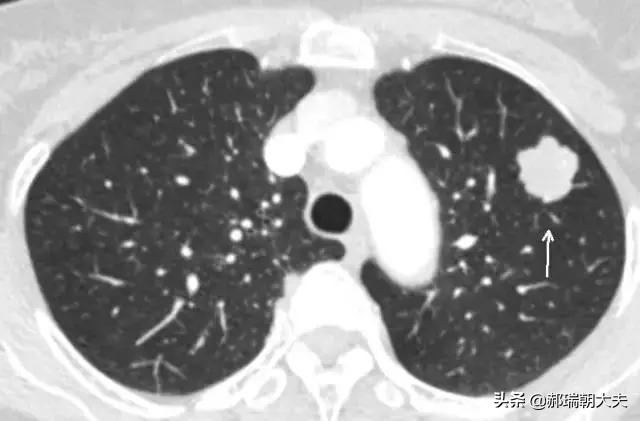

健康診断への意識が高まるにつれ、肺結節が発見される人が増えている。肺結節とは画像診断の用語で、肺結節の画像上の定義は、肺実質に完全に囲まれた、境界明瞭な小さな病変(直径≤30mm).結節の形態は、固結または亜固結に分類される。亜固結はさらに、純粋なすりガラス結節と部分的な固結に分類される。直径30mmを超える病変は結節ではなく腫瘤であり、悪性の可能性が高い。

肺結節の約99%は良性病変である。一般的な原因としては、感染性肉芽腫や良性腫瘍(肺悪性腫瘍など)、時には血管や炎症性病変が挙げられる。肺結節の約1%が悪性である。悪性肺結節の一般的な原因としては、原発性肺癌、肺転移およびカルチノイド腫瘍が挙げられる。

結節の直径は悪性腫瘍の独立した予測因子であることが研究で示されている。結節の直径が大きいほど悪性腫瘍のリスクは高く、以下の確率がある:結節の直径<5mm:<1%;结节直径为5-9mm:2%-6%;结节直径为8-20mm:18%;结节直径>20mm:>50%。